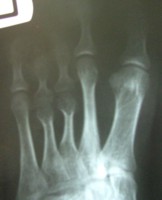

این عمل در مرکز جراحی ولنجک و زیر نظر دکتر حقانی فوق تخصص دست صورت گرفته

تاریخ عمل  پنج شنبه 20 شهریور 1393

شست کوتاه